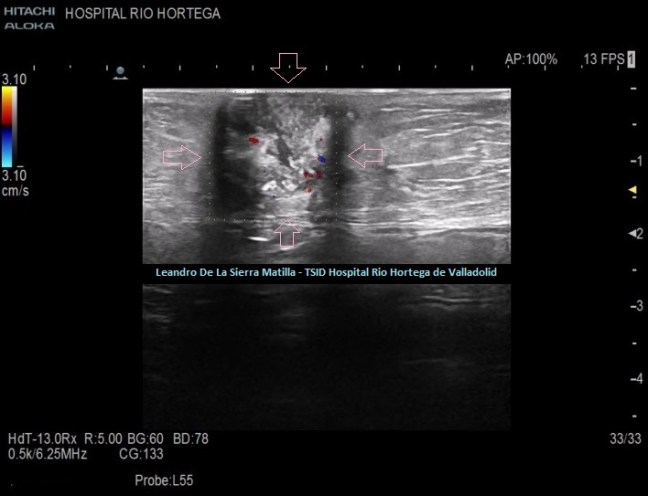

Os quiero presentar a Leandro De La Sierra Matilla, es TSID en el Hospital Rio Hortega de Valladolid, y nos resenta un precioso caso que tengo el honor de subir al Blog como una colaboración que espero, sea la primera de muchas, Leandro, haces la ecos, igual que tocas y cantas, el arte se lleva por dentro, amigo…millones de gracias…

Con el epónimo de nódulo de la hermana Mary Joseph se conoce, desde 1949, al nódulo metastásico umbilical producido por un adenocarcinoma primario intraabdominal.

El nódulo de la hermana Mary Joseph aparece, según artículos de revisión, entre el 1 y el 3% de los casos de neoplasias intraabdominales. Su tamaño no sobrepasa los 4-5 cm de diámetro, de aspecto sólido, irregular y no doloroso, pudiendo llegar a ulcerarse produciendo un exudado de contenido hemorrágico o purulento con salida al exterior.

Semiología Ecográfica

Esta LOE (lesión ocupante de espacio) es principalmente hipoecogénica ( aunque podemos encontrar ecogenicidad híper -iso-hipoecogénica), marcadamente heterogénea, sólida (descartando así un absceso), no tiene contenido de asas intestinales ni de grasa (descartamos una hernia), con bordes mal definidos y con flujo doppler en su interior, situándose dentro de la cavidad umbilical.

Caso clínico

Presentamos el caso de una mujer de 83 años de edad que acude a la consulta de ecografía remitido por su médico de familia por un aumento del volumen abdominal de pocos meses de evolución, sin ningún otro síntoma.

Se realiza estudio de Ecografía Abdominal protocolizado, en el que se observan entre otros hallazgos, varias lesiones esplénicas y ováricas (flechas rosas) junto con una mínima cantidad de líquido libre abdominal.(FIG 1,2 y 3)

Durante el estudio del peritoneo, retroperitoneo y cadenas linfáticas abdominales, observamos una lesión superficial, redondeada, heterogénea, hipo-Isoecogénica con zonas hiperecogenicas, de aspecto sólido.(FIGURA 4)

4

Cambiamos a una sonda lineal para un estudio más detallado, observando una LOE hipoecogénica con zonas híper-isoecogénicas, heterogénea, sólida, sin contenido de asas intestinales ni de grasa, con bordes mal definidos y con flujo doppler en su interior, ubicada dentro de la cavidad umbilical (FIGURAS 5, 6 Y 7)

5

6

7